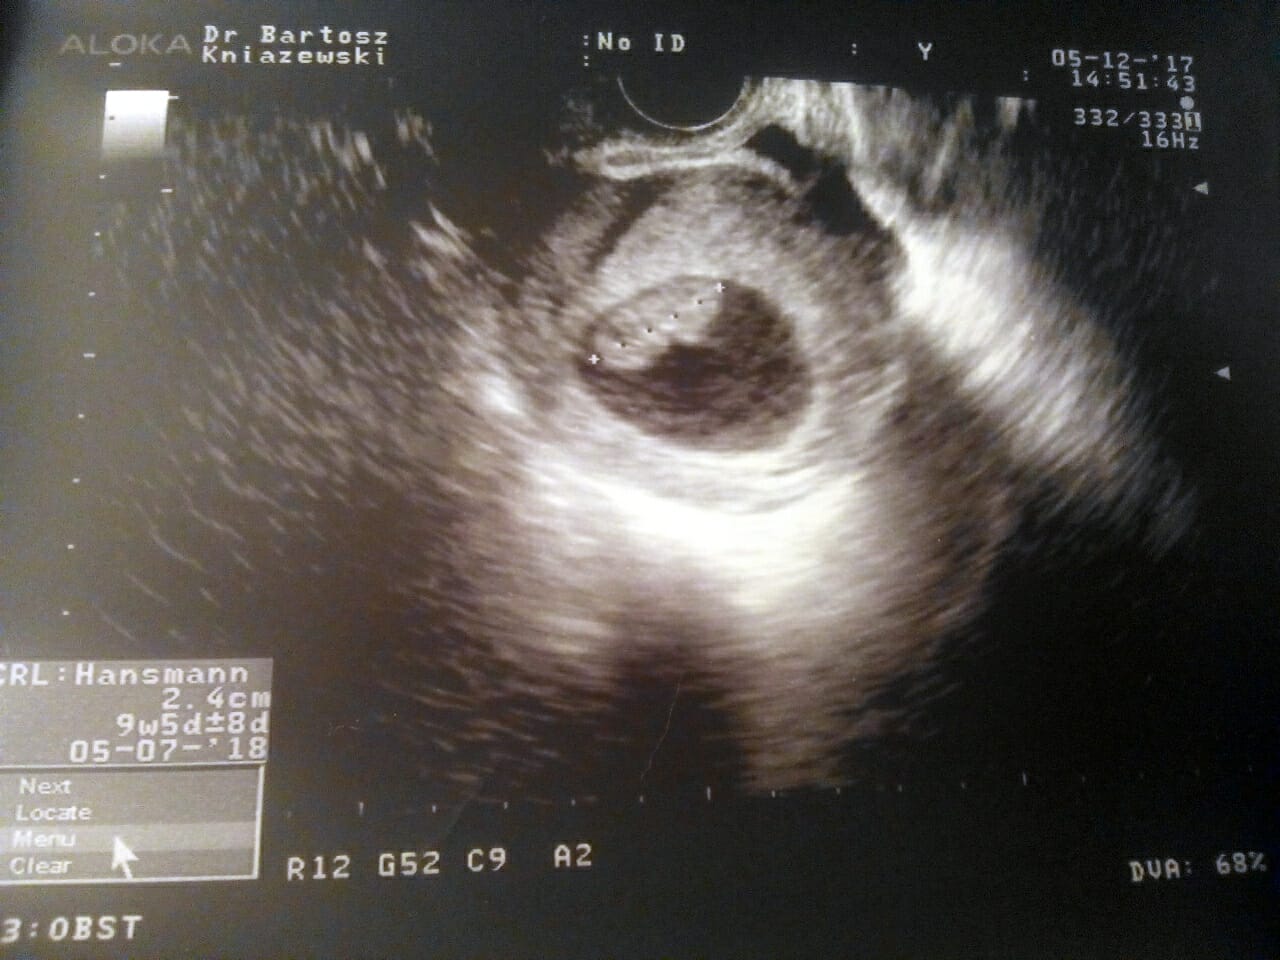

Powiedzcie mi czy tutaj coś więcej widać niż pęcherzyk?

Wcześniej nie miałam nic w środku pecherzyka.

Nie znam się dlatego pytam

Dzisiaj weszłam w 7 tydzień dokładnie